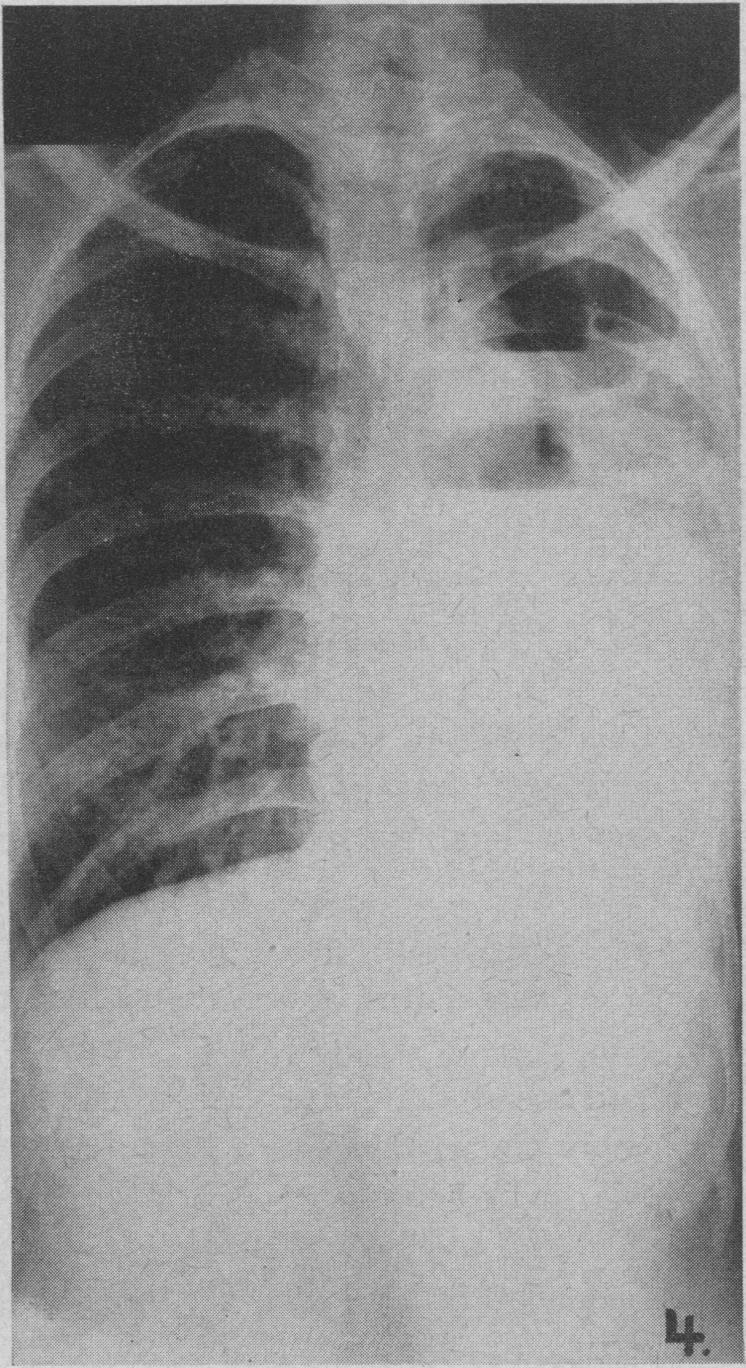

Congenital cystic adenomatoid malformation of the lung in infants.

Am J Roentgenol Radium Ther Nucl Med. 1956 Sep;76(3):516-26.